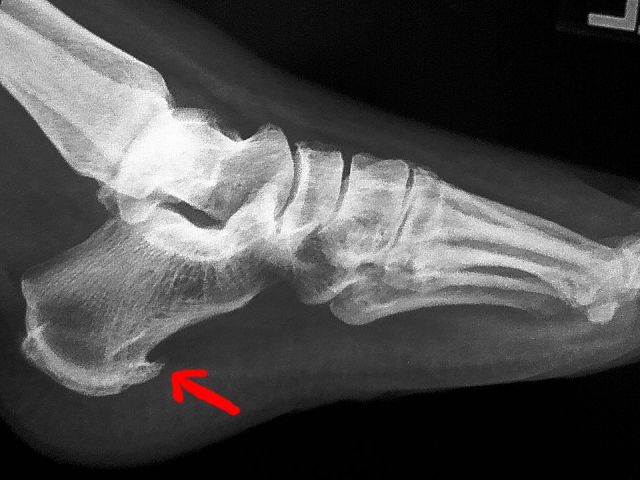

最近一段时间,王老先生双侧足跟持续疼痛。开始时他没当回事,谁知越来越严重,到医院拍片后,发现一侧有骨刺,另一侧也有骨刺

骨刺是由于构成关节的软骨、椎间盘、韧带等软组织变性、退化,关节边缘形成骨刺。就像自行车需要有一个支架才能放稳一样,当骨骼周围的肌肉韧带没办法提供足够的支撑的时候,骨骼的正常受力就会改变,为了不被压断,骨头会自行加固,逐渐长出一个支撑点来保持稳定。

随着年龄增加,每个人或多或少都会有长骨刺的情形,而X光上出现骨刺也不见得就需要接受治疗,只有在骨刺压迫到神经引起其他症状时,才需要进一步接受治疗。